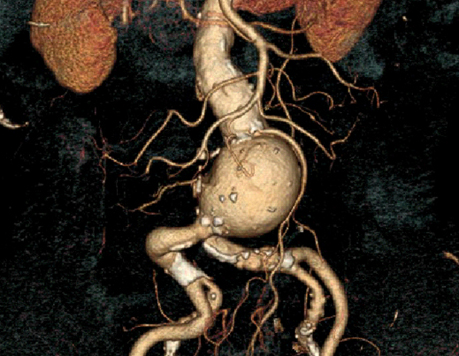

Les anévrismes de l’aorte abdominale (AAA) sont une dilatation excessive et pathologique de l’aorte dont le principal risque est la rupture. Le diamètre normal d’une aorte abdominale se situe entre 15 mm et 25 mm suivant le sexe et l’âge du patient.

bituellement, les patients porteurs d’un anévrisme ne présentent aucun symptôme. Cet AAA est découvert le plus souvent de manière fortuite lors d’un examen (échographie, scanner) réalisé pour une autre raison médicale. L’évolution naturelle d’un anévrisme est sa progression avec une augmentation de taille variable selon les individus. L’anévrisme est soit fusiforme soit sacculaire (en forme de sac). C’est dans l’aorte abdominale en dessous des reins que les anévrismes sont les plus fréquents.

Le meilleur facteur prédictif de rupture connu actuellement est le diamètre maximal de l’anévrisme. Plus l’AAA est volumineux plus il a de risques de se rompre. Cette rupture d’anévrisme peut entraîner jusqu’à 85 % de mortalité. En cas de rupture, 50% des patients toujours en vie lors de leur transfert dans un hôpital décèdent. Ce risque de rupture est faible pour les petits AAA et augmente de manière significative à partir de 55mm de diamètre qui est considéré comme le diamètre à partir duquel l’anévrisme peut ou doit être pris en charge. Au-delà de 55 mm le taux de rupture est de 10% par an et augmente avec la taille pour atteindre 30% pour les AAA supérieurs à 7cm. Dans certaines conditions (anévrisme douloureux, anévrisme sacculaire, anévrisme dans la famille, patients de sexe féminin) les AAA doivent être traités à partir de 50 mm.

La détection ciblée des AAA est recommandée chez les hommes de 65 à 75 ans fumeurs. L’échographie abdominale est l’examen de choix. Lorsqu’un AAA est détecté et que sa taille est importante, l’examen le plus utile pour bien analyser la morphologie de l’anévrisme aortique est un scanner abdominal avec injection de produit de contraste (angio-scanner). Cet examen permet de bien voir les autres artères et en particulier de mesurer la distance qui existe entre les artères rénales et l’anévrisme.

Lorsque le diagnostic d’AAA de taille significative est avéré et que l’état général du patient est satisfaisant, une intervention chirurgicale doit être proposée. Dans 60% des cas, un traitement endovasculaire est réalisable. Ce traitement endovasculaire consiste à exclure l’AAA par une endoprothèse qui est introduite par les artères fémorales au travers de la peau ou via une très courte incision aux plis de l’aine. Cette endoprothèse est un tube bifurqué synthétique renforcé par des mailles métalliques (stents). L’endoprothèse est initialement repliée dans une gaine qui est positionnée correctement au niveau de l’aorte sous contrôle radioscopique (rayons X). Cette endoprothèse est ensuite libérée de sa gaine et déployée jusqu’au niveau des artères iliaques par une manipulation à l’extérieur du patient.